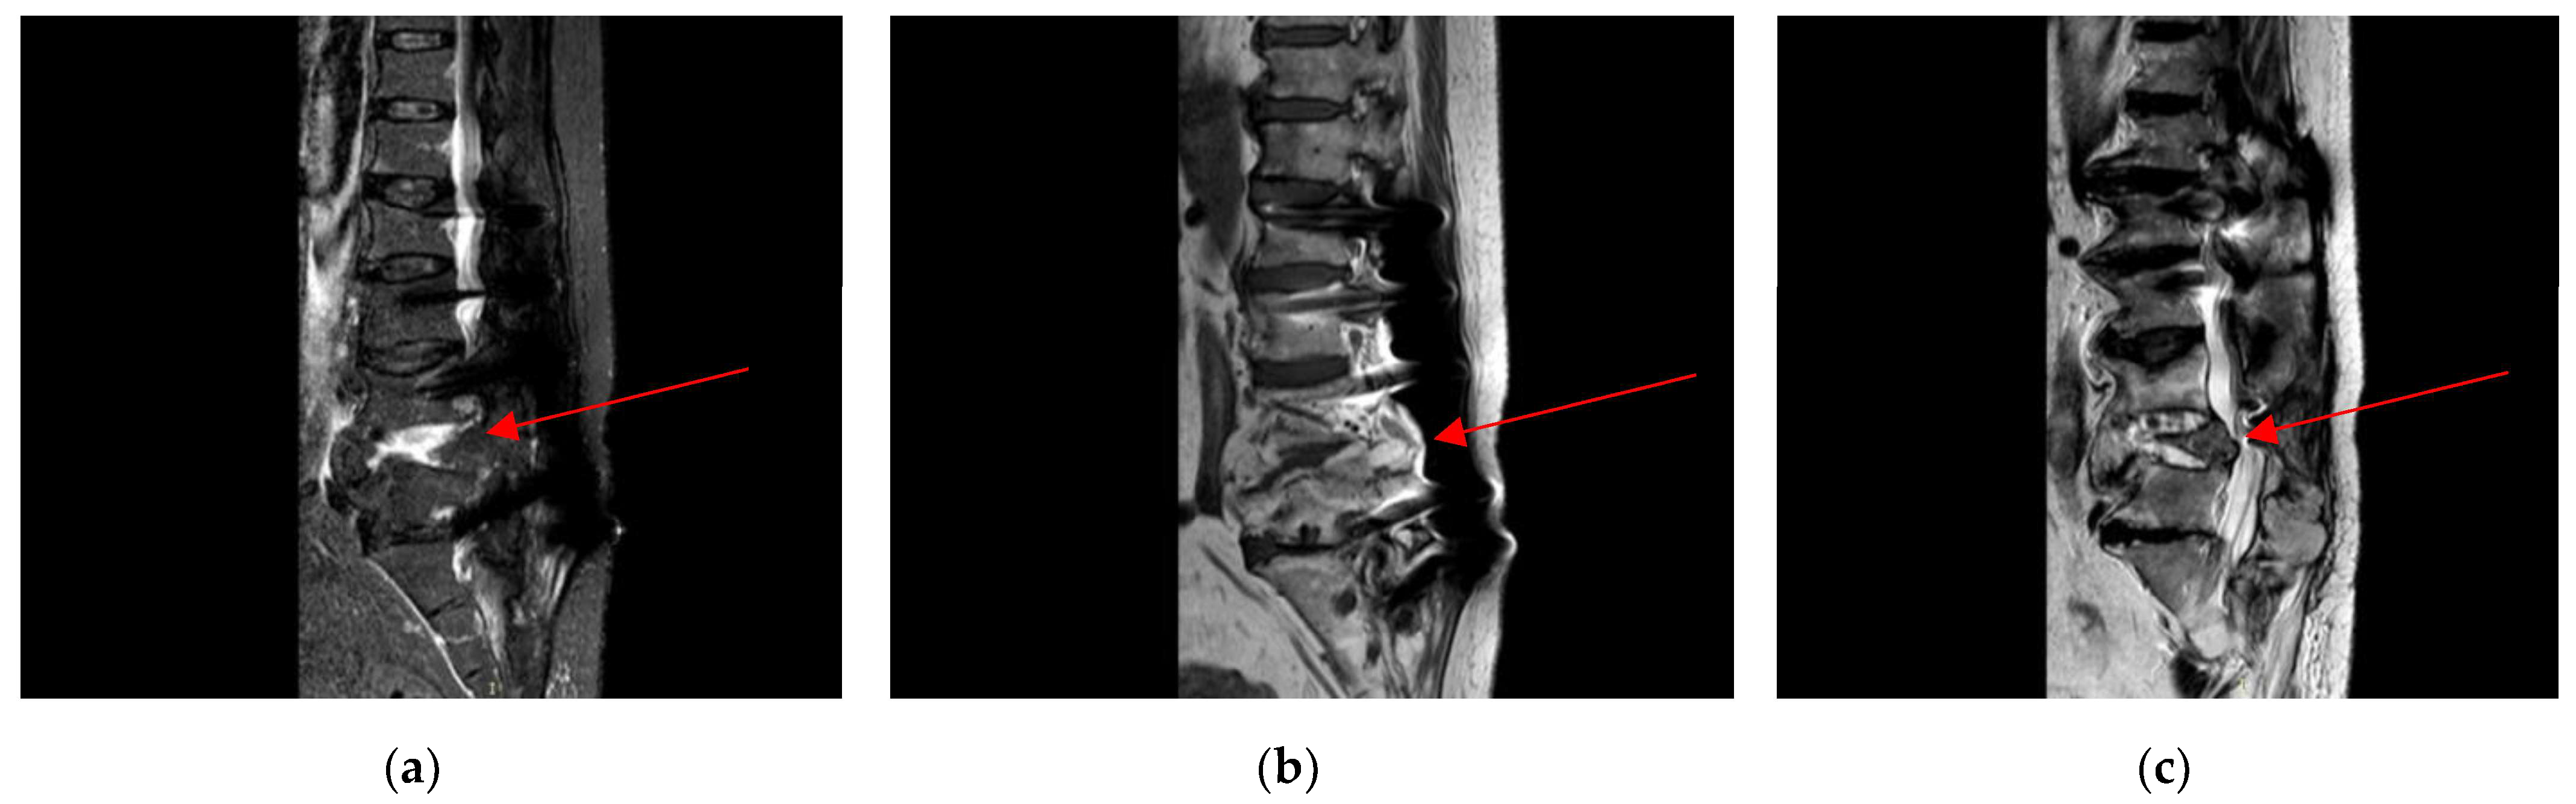

2.3. Admission to Infectious Diseases Unit

2.4. Neurosurgery Evaluation